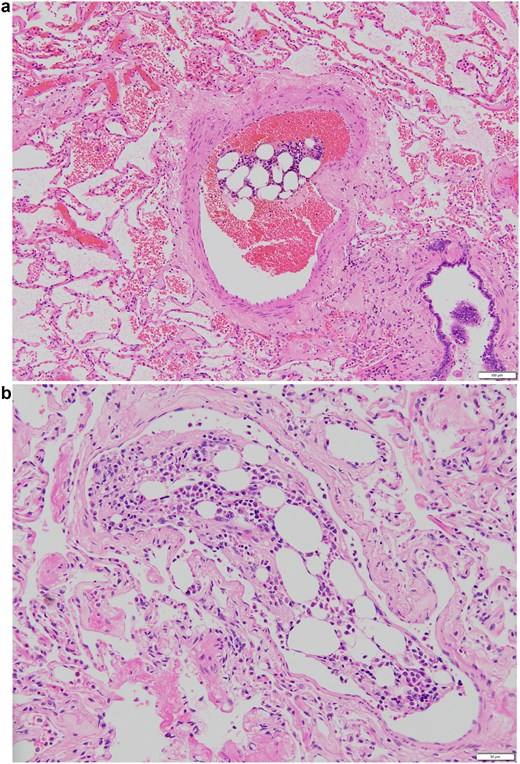

Pathological examination of the resected specimen revealed lung adenocarcinoma. Multiple bone marrow emboli, consisting of fat droplets and bone marrow cells, were identified in the pulmonary arteries of the resected lung (Fig. 3). The size of the emboli varied, and some of the larger emboli measured over 500 mm in diameter on histological sections. There were no fractures other than the rib fracture, suggesting that the intraoperative rib fracture caused bone marrow embolism. Five months after surgery, the patient had no respiratory problems.

Representative images of embolism in the pulmonary artery. (a) An embolism in the relatively large pulmonary artery. The size of the embolism was 540 × 200 mm. (b) An embolism in the pulmonary artery in high-magnification view. The pulmonary embolism measured 290 × 160 mm in diameter.